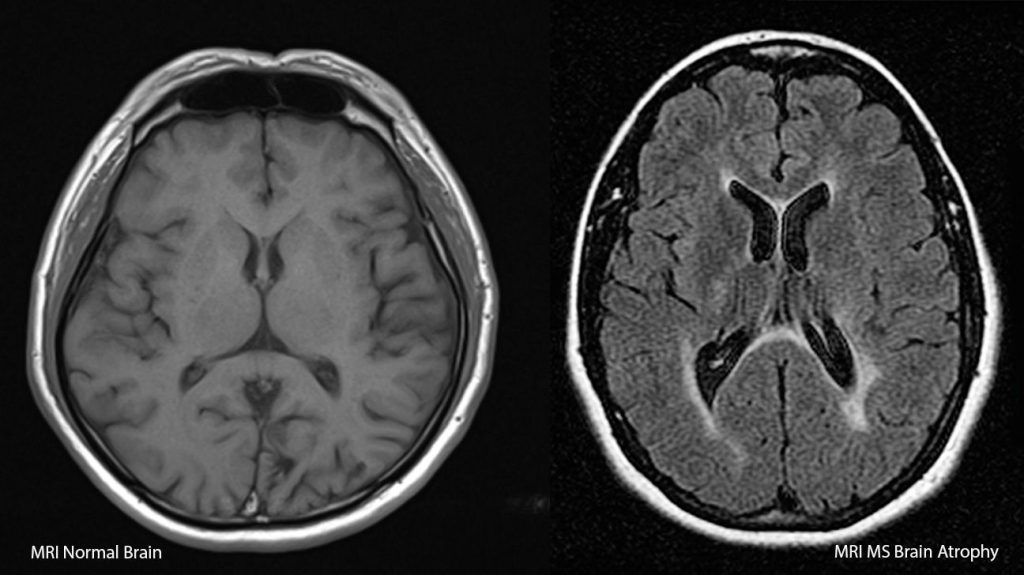

Diagnosis MS merupakan proses yang kompleks karena gejalanya bisa mirip dengan kondisi medis lainnya. Dokter biasanya melakukan anamnesis dan pemeriksaan fisik untuk mengidentifikasi gejala dan riwayat kesehatan pasien. Selanjutnya, pemeriksaan penunjang seperti MRI dan tes darah digunakan untuk memastikan adanya kerusakan mielin.